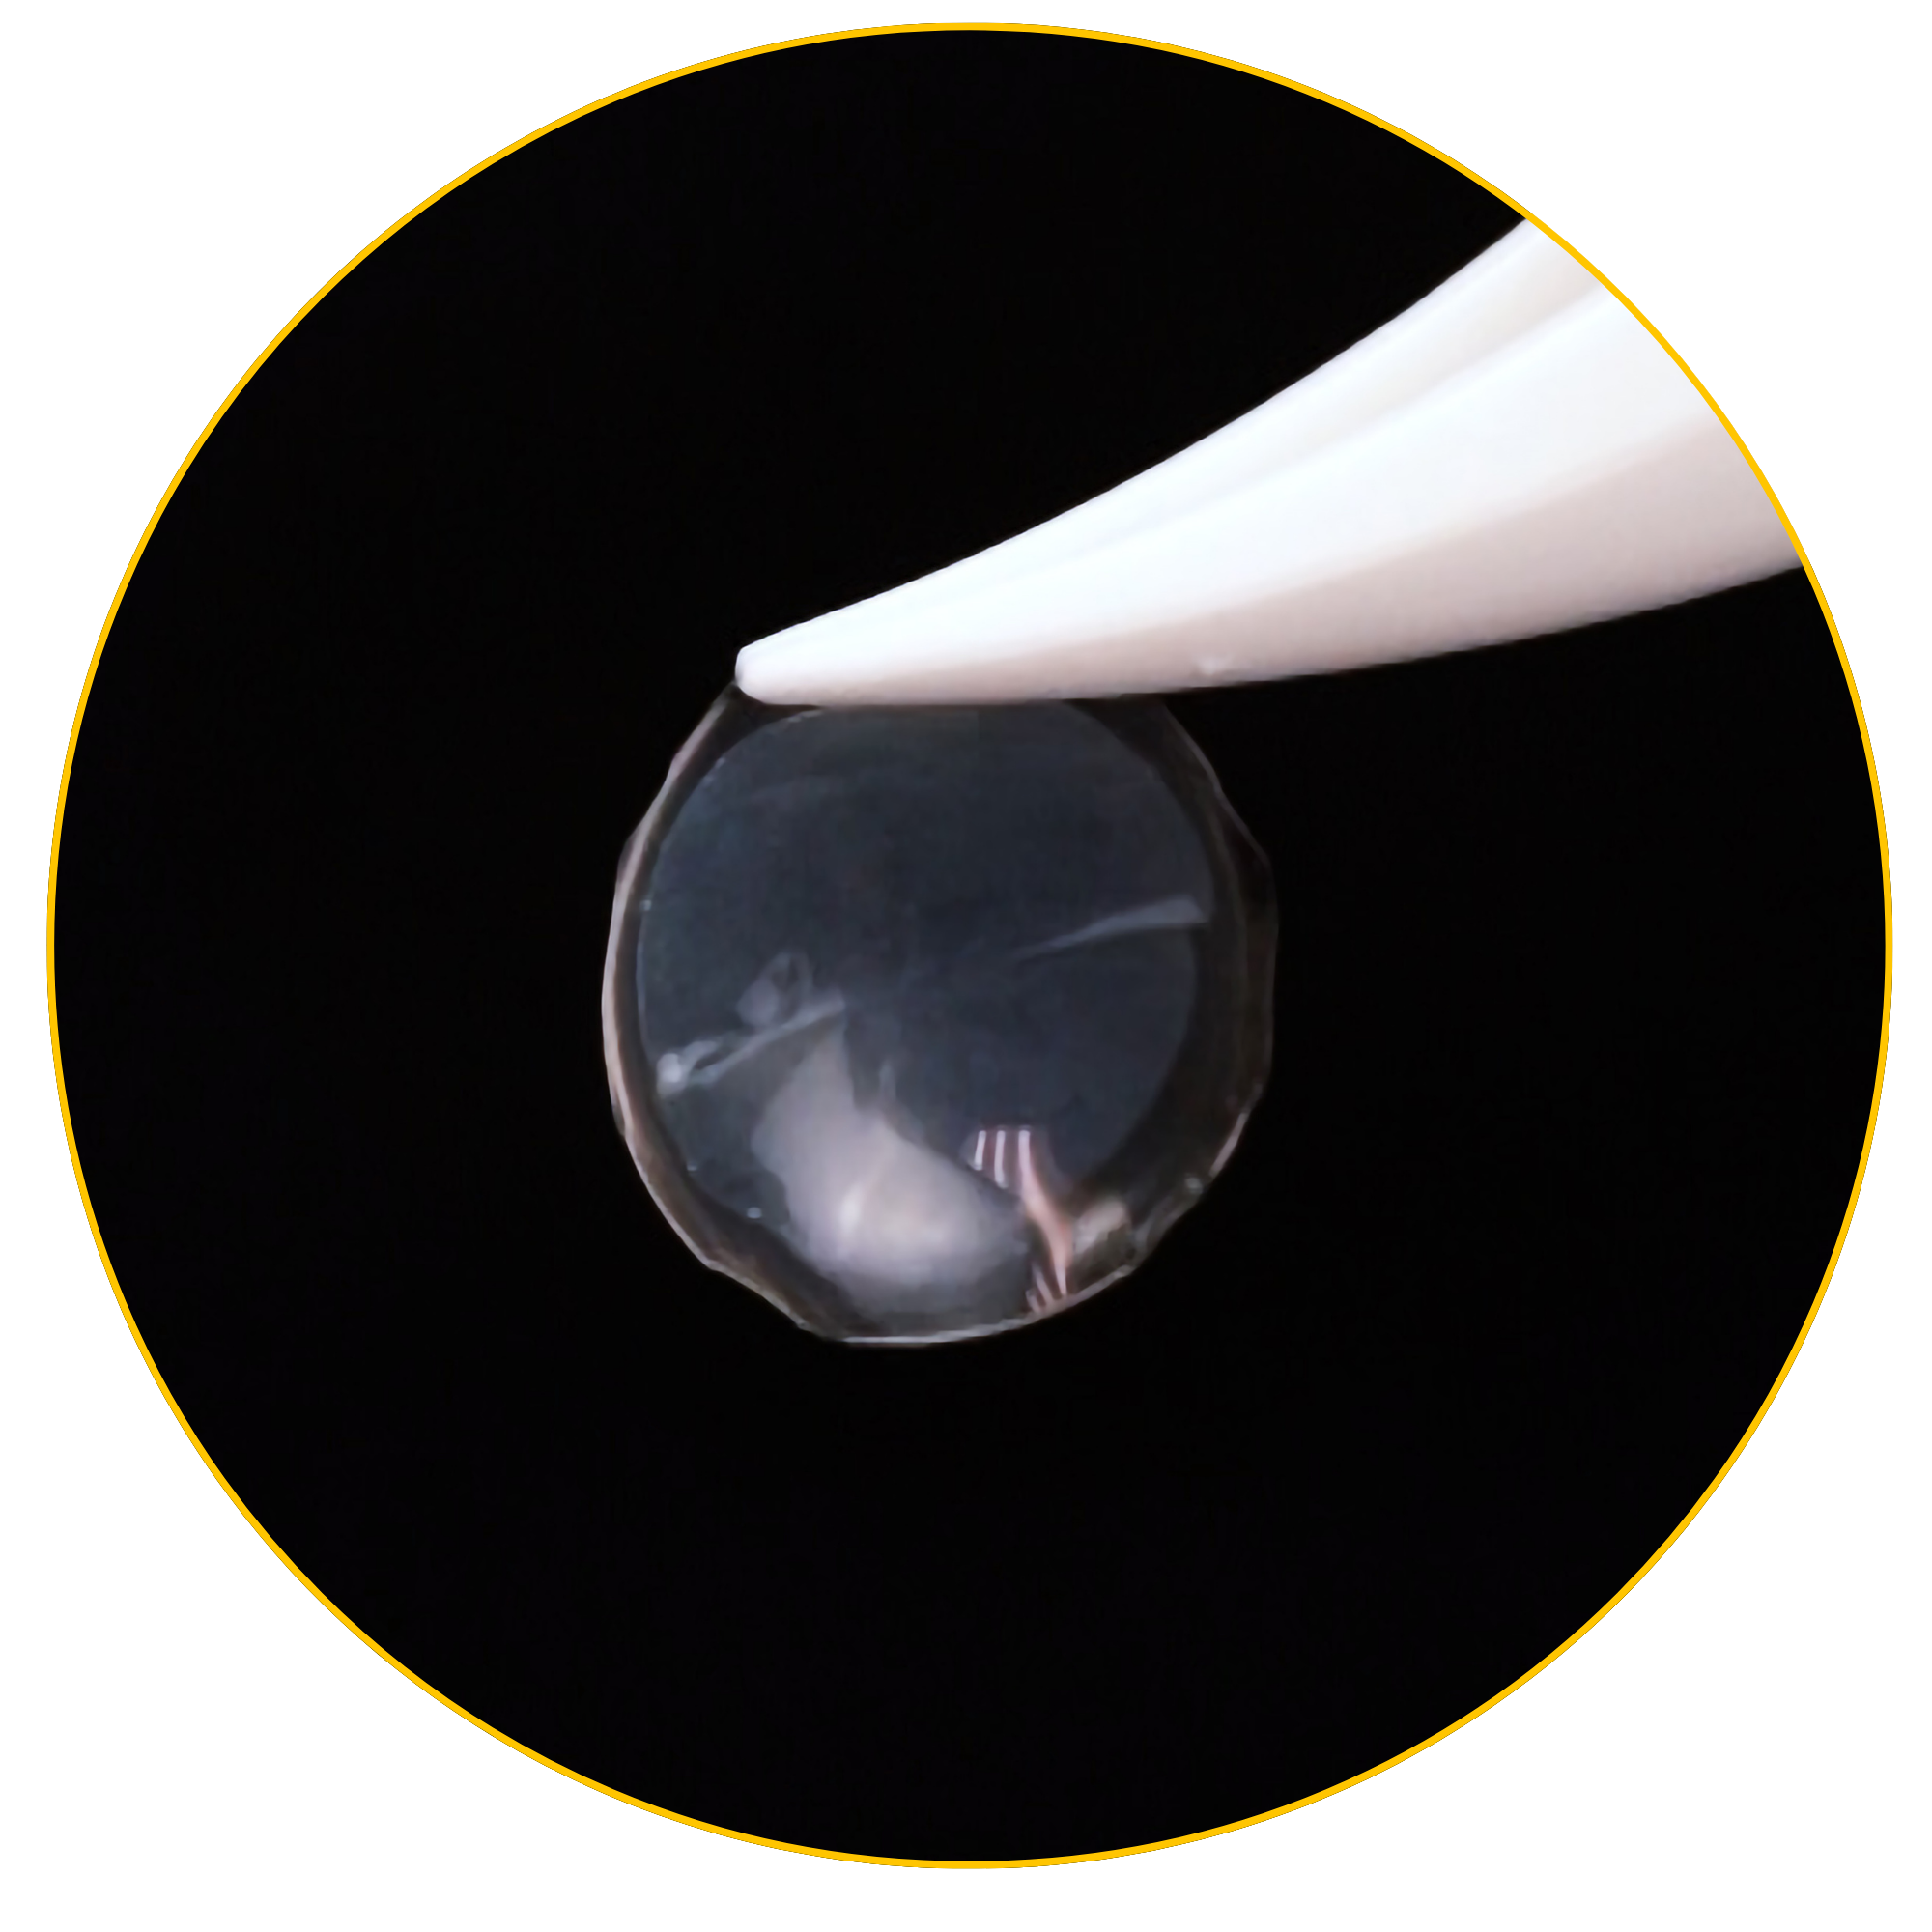

The American Academy of Ophthalmology (AAO) recognizes Prokera, a self-retained Cryopreserved Amniotic Membrane (CAM) device, as a Stage 1 treatment option for Neurotrophic Keratitis (NK).2

CAM preserves innate complexes found in amniotic membrane tissue that help support the regeneration of corneal surface.8,9 In a clinical study, CAM is shown to reduce signs and symptoms in ocular surface disease and restore corneal nerve density, helping improve corneal sensitivity in patients with Dry Eye Disease. 7

Products like Prokera and CAM360 AmnioGraft give physicians a convenient, in-office treatment for patients with NK. Early intervention using Cryopreserved Amniotic Membranes may protect the cornea and support nerve regeneration.